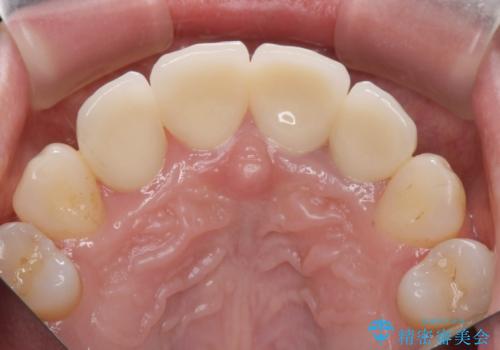

自然な歯の色に仕上げることができ、大変喜んでいただくことができました。

- 52.8万円(ジルコニアクラウン×4・仮歯×4)費用は治療当時の料金となります